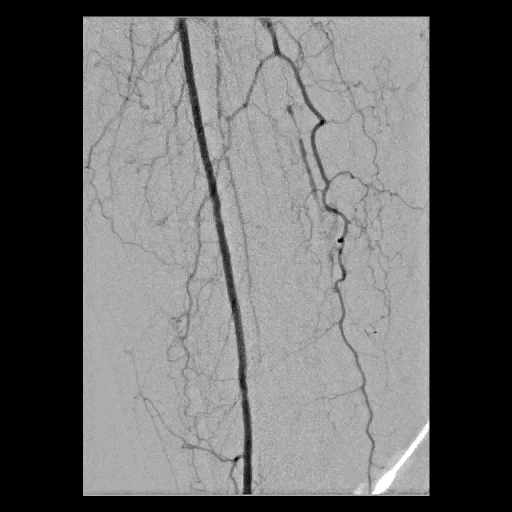

Figure 2.  左小腿血管的經皮腔內血管成形術治療

A. 左側膝蓋下血管多條阻塞

B.經皮腔內血管成形術後,重建多條血管